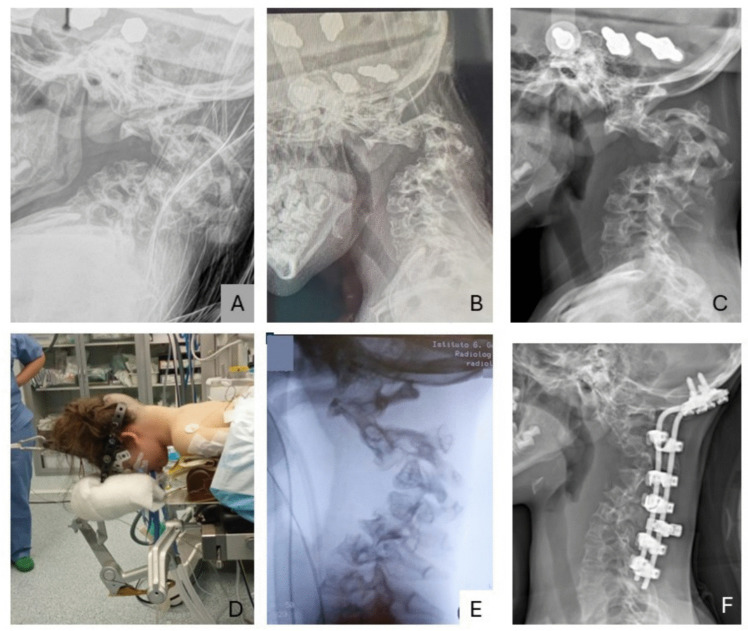

Purpose: We faced and herein report a detailed description of pre-operative assessment, management, and post-operative follow-up of a 2-year and 10-month-old girl with neurofibromatosis 1 (NF1) who presented with severe, dystrophic, cervical kyphosis (170 degrees) associated with extensive pre- and para-vertebral plexiform neurofibromas, who also went under MEK inhibitors therapy. Cervical kyphosis in NF1 is particularly rare, and there is no extensive literature available on the subject in terms of clinico-radiological features, surgical approach, and outcomes. We therefore also performed a comprehensive review of the available literature on the topic.

Results: Our patient underwent a first-stage halo-gravity traction followed by a single-stage occipito-cervical posterior fusion. The six-week traction resulted in a reduction of the deformity from 170 to 90°. A further amelioration was obtained by surgery with a final 60% correction of the curvature (69° at last post-operative X-ray). No complications were observed at 1-and-a-half-year follow-up. The plexiform neurofibromas were treated with MEK inhibitors: trametinib for 1 year and 11 months until performing halo traction, and with selumetinib after surgery. We just found 19 papers suitable according to our selection criteria.